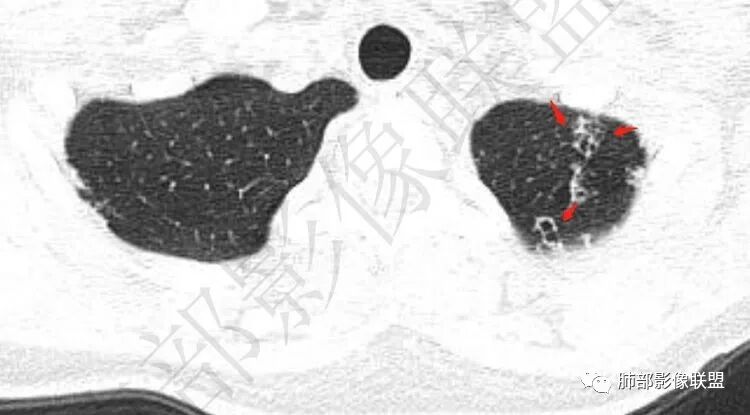

【每日晨读】双肺上叶多发薄壁空洞

两肺多发囊或空洞(部分腔内不干净可见间隔影)+多发结节 (右侧胸膜下的结节显著)+左肺尖斑片影。年轻女性,体检发现。考虑结核?鉴别PLCH(奇异囊加结节,吸烟男性多见),转移瘤(要有原发肿瘤病史)

年轻女性,血常规正常,体检发现,影像表现:双上肺多发空洞及空腔样改变,薄壁为主,部分壁不规则,伴不规则分隔,疑似鬼脸征,多数位于胸膜下。诊断:1、隐球,年轻女性,体检发现,血常规正常,多数胸膜下,疑似鬼脸征,必须首先考虑。2、结核,发病部位支持,多发空洞样病变支持,但无临床症状,病灶形态太单一,无树芽征,可能性不大。3、PLCH,无吸烟史,无临床症状,可能性小。4、寄生虫,无嗜酸增高,无IGE增高,可能小,5、空腔性转移,无原发灶,年轻较小,暂不支持。6、多中心原发腺癌,空腔周围无明确边界清楚的GGO,年轻。可能小。7、NTM,无支扩,可能小。8、风湿类疾病,无相关病史,无相关自身抗体结果,暂不支持。综上,考虑隐球菌可能大。先查隐球荚膜抗原。必要时穿刺活检。

大雄: 青年女性,双上肺多发不规则薄壁空洞伴少许结节,部分洞内有分隔,病灶多位于胸膜下,无症状,血象正常。影像比较怪异,可能得疾病谱有:隐球,结核,寄生虫,NTM,类风湿结节,空洞型转移,PLCH结核无明显气道播散树芽,寄生虫嗜酸细胞不高,NTM无症状,类风湿结节与转移少见上叶优势分布,PLCH一般有吸烟史。综上,先考虑隐球菌,建议查隐球抗原

2.双肺多发薄壁空洞影、条索影及结节影,边界较清楚,密度偏高不柔和,散乱,但有成簇倾向或堆积感,胸膜下分布为主,双肺上叶分布为主。

3.空洞相当不规则,缺乏张力,未见血管穿行,未见壁结节,未见液平。

1.年轻女性,缺乏临床表现,多发空洞及结节影、条索影,上肺胸膜下分布为主,临床实践中常见肺病是什么?正如部分老师分析的—继发性肺结核!